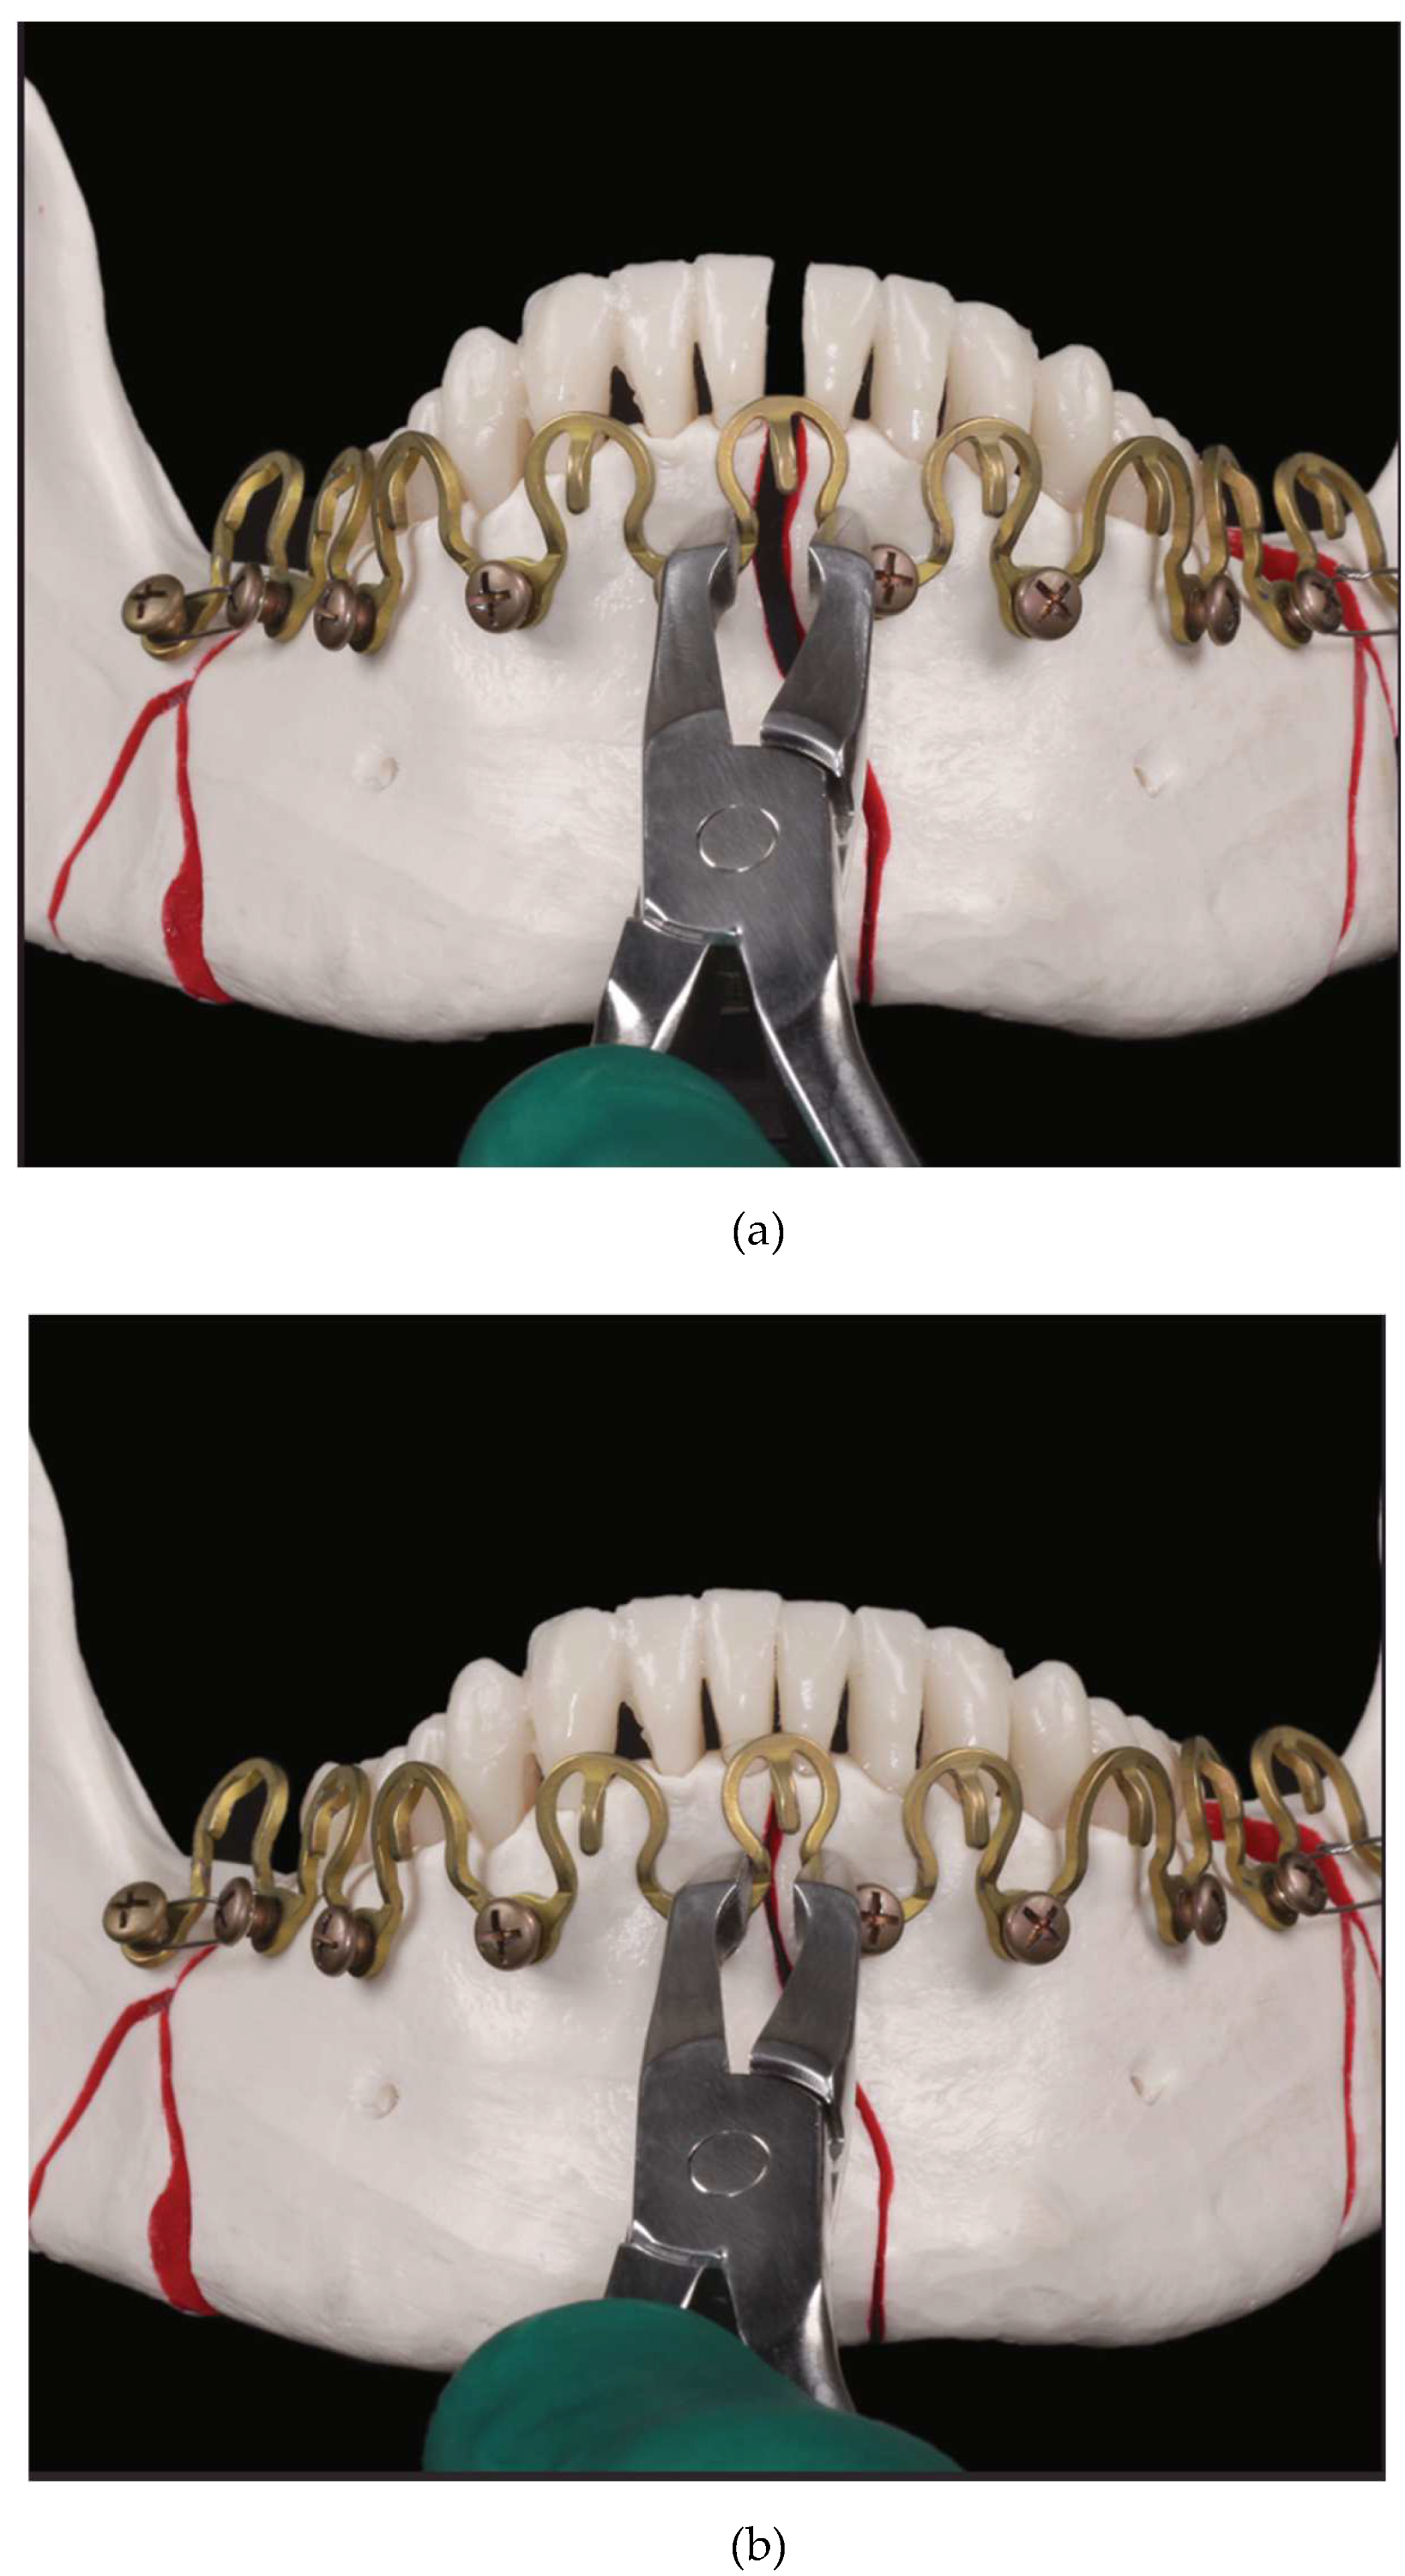

Figure 4.

Initial schematic draft of basic concept of a wave-line MMF device - A pair of full arch 5 segments wave “plates” installed in the mandible and maxillae oriented diametrically opposed to each other in a harmonic upwardly and downwardly alternating oscillation pattern of crests and troughs. The interfaces and hooks for interarch/intermaxillary connection relate vis à vis at the level of the tooth equators. The plate holes for bone fixation are intended to lie outside the dentition, below or above, the alveolar processes with their underlying tooth roots. (Modified

Figure 1 from United States Patent, Patent No.: US 2011,0152946 A1 – 23 June 2011 and

Figure 1 from United States Patent, Patent No.: US 10,130,404 B2 2018 – 20 November 2018).

Source/origin of Figure 4: US Patent, Patent No.: US 2011,0152946 A1 – 23 June 201137.